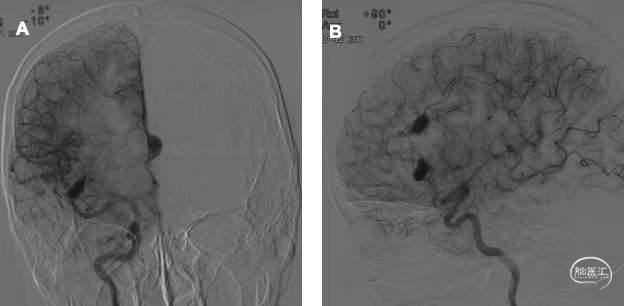

入院后DSA检查见右侧大脑前动脉A3段及大脑中动脉M3段局部梭形膨大(图2)。梭形动脉瘤无法按常规方式夹闭瘤颈,需闭塞载瘤动脉。考虑大脑前动脉动脉瘤位于胼周动脉主干,闭塞可能造成功能障碍,而中动脉动脉瘤位于非功能区,故于手术前先行右侧大脑前动脉球囊闭塞实验。在局麻下,全身肝素化,双侧股动脉穿刺置鞘,将导引导管置入至右侧颈内动脉岩骨段,取球囊1枚超选入右侧大脑前动脉A3段,在动脉瘤近端充盈球囊,造影见球囊远端动脉无显影,提示闭塞良好(图3)。另取一造影管超选至左侧颈内动脉、左侧椎动脉造影,未见明显血流逆向充盈动脉瘤。共闭塞20min,过程中患者无明显不适,对答良好,四肢肌力无下降。

图2. 脑血管造影图像 2a为正位,2b为侧位,示右侧大脑前动脉A3段、大脑中动脉M3段梭形动脉瘤。